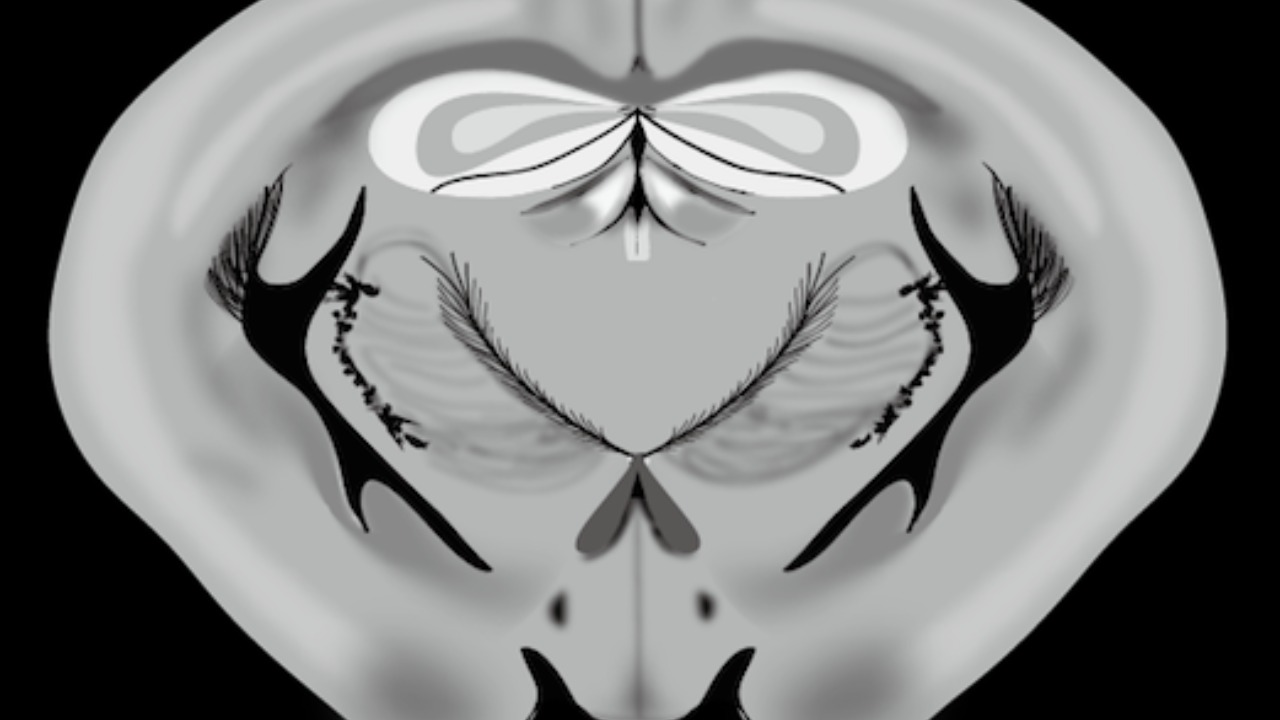

Key Discoveries from the AI-Generated Map

The AI-generated map led to several novel discoveries, including the identification of rare neural cell types and unexpected synaptic connections in the mesopontine tegmentum. These findings could have implications for understanding sleep-wake cycles and other neurological functions (Live Science). Quantitative insights from the study revealed the mapping of 150,000 cells and 200 million synapses within the 1 mm³ volume, indicating a denser neural wiring than previously anticipated (Neuroscience News).